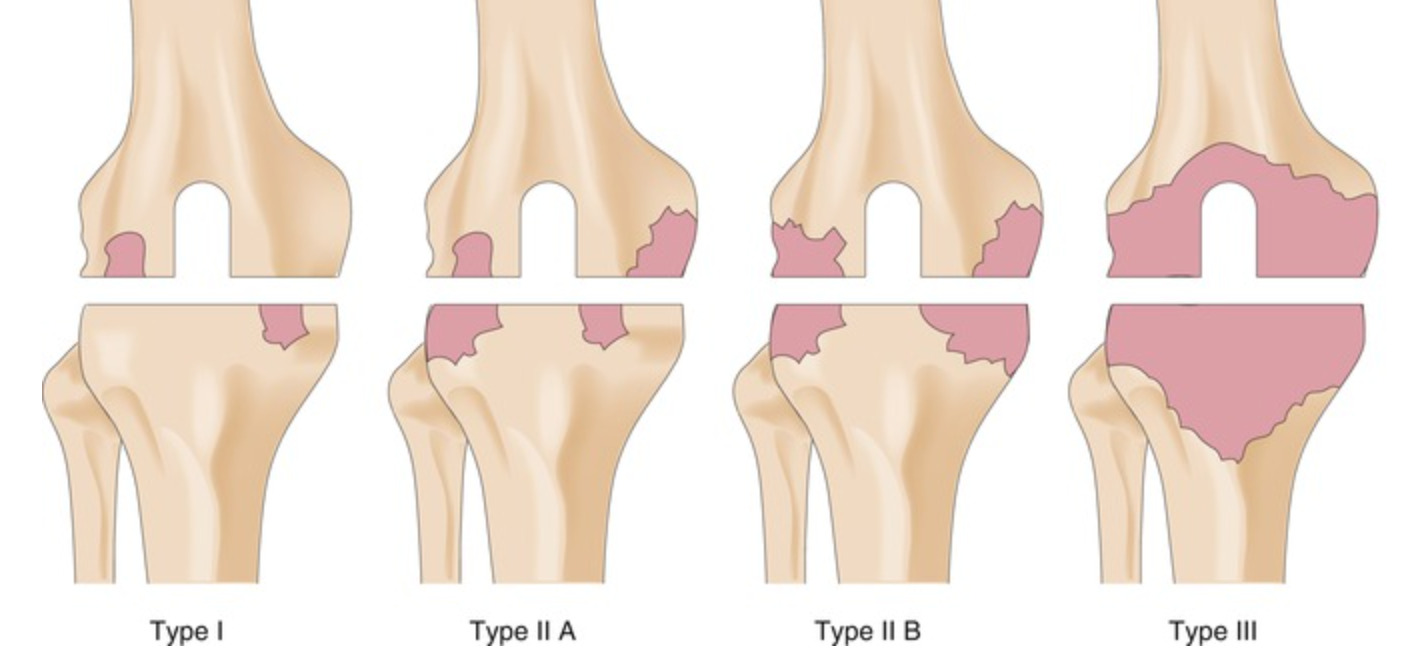

AORI骨缺损分型